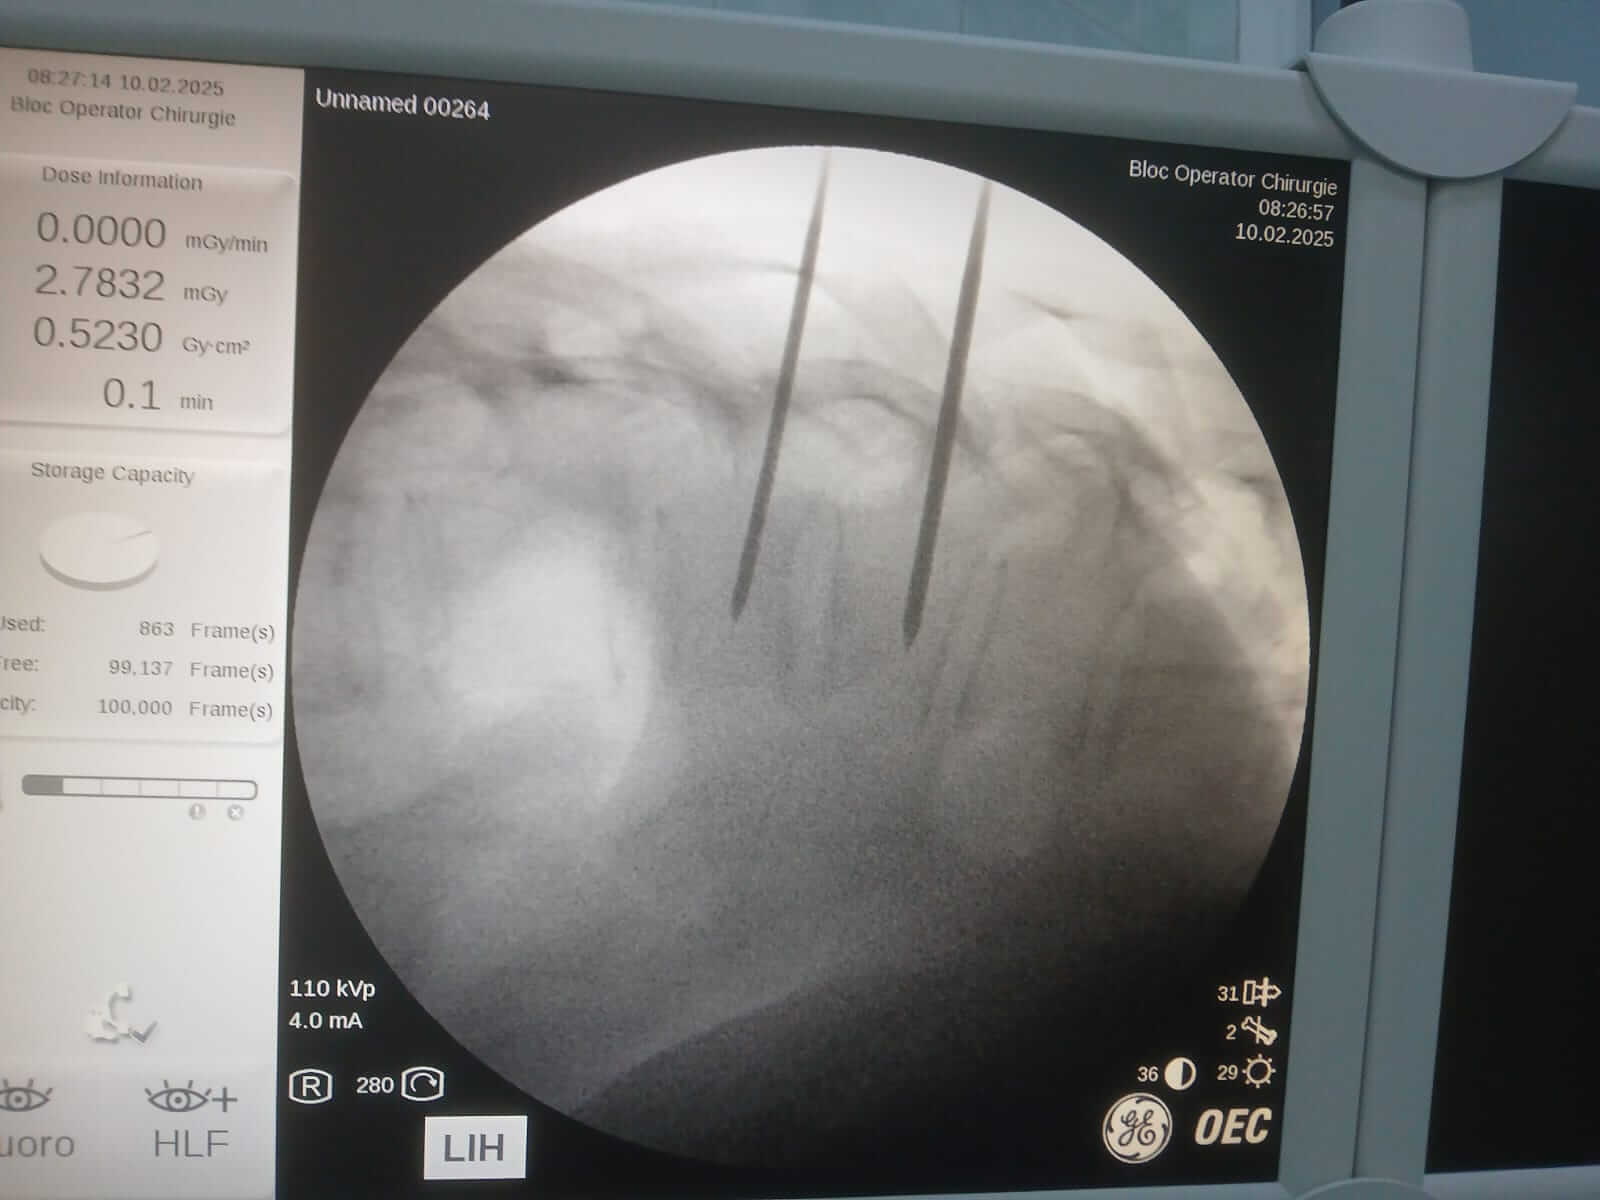

În data de 10 februarie 2025, la Spitalul Județean de Urgență Buzău a avut loc o intervenție neurochirurgicală în premieră. Este vorba despre o intervenție de vertebroplastie percutană, sub control radiologic.

În urma investigațiilor efectuate, au fost identificate două fracturi, prin tasare ale corpurilor vertebrale toracale T11 și T12, fiind nevoie urgent de intervenție neurochirurgicală. După ce a aflat diagnosticul, pacienta și-a exprimat acordul de a efectua intervenția în unitatea noastră.

În premieră la nivelul județului Buzău, s-a intervenit neurochirurgical prin procedura denumită „vertebroplastie percutană sub control radiologic”. Operația a durat 30 de minute iar pacienta s-a recuperat complet, cu externare în aceeași zi, post procedural.